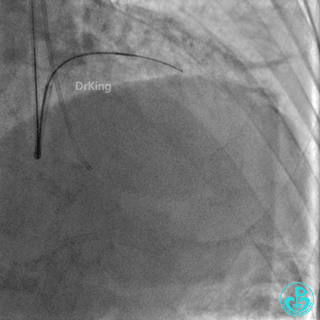

右桡动脉入路6F EBU 3.75指引导管到位,Corsair 150微导管辅助,Sion导丝尝试通过侧支。

Corsair微导管跟进困难,换Finecross 150微导管,通过侧支到达前降支闭塞远端血管真腔。